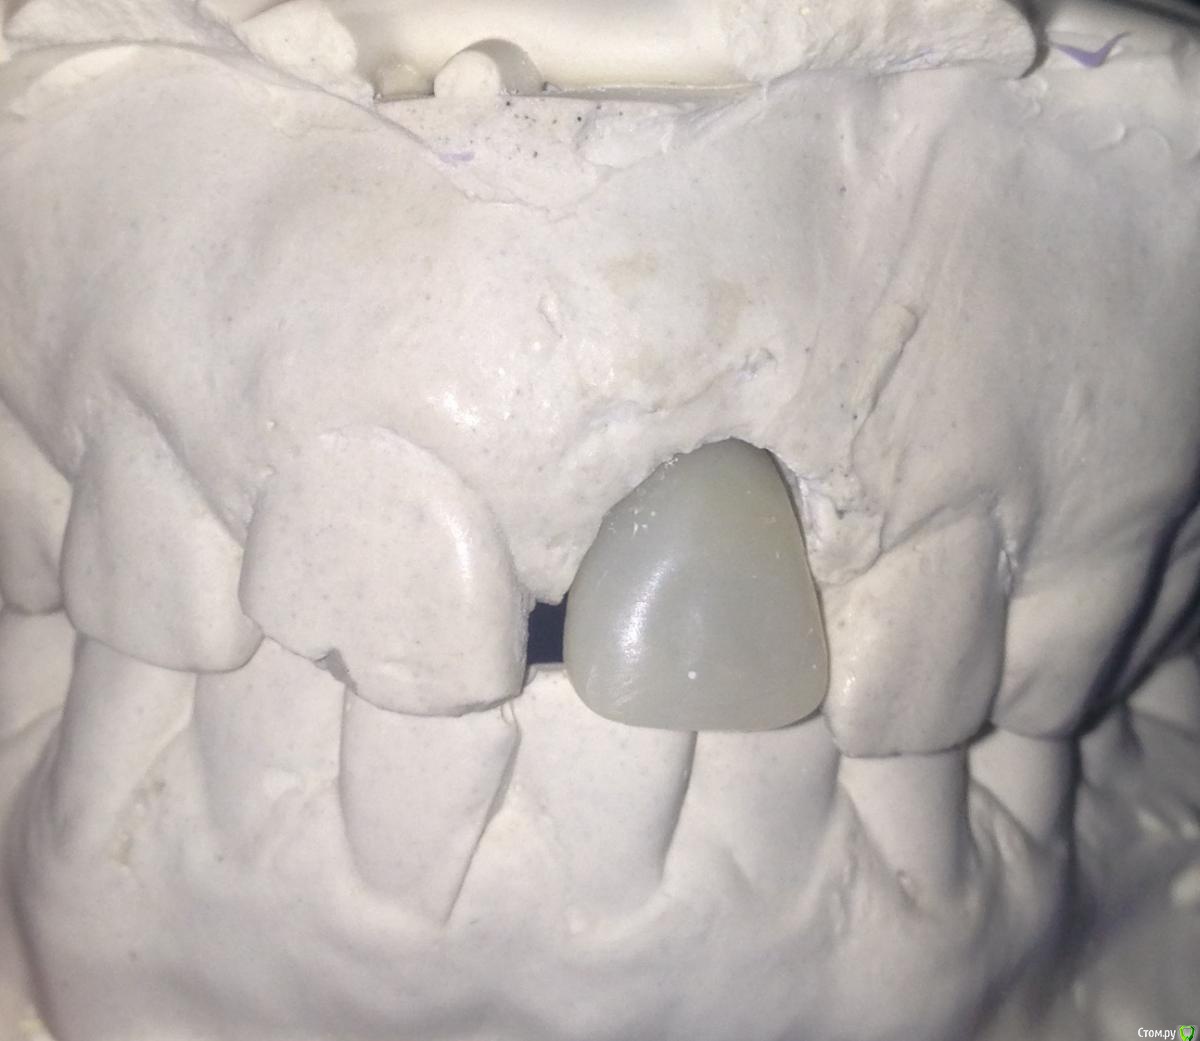

Популярный пост Фарид Расулыч Опубликовано 20 декабря, 2014 Популярный пост Поделиться Опубликовано 20 декабря, 2014 (изменено) Пациент обратился с проблемой, на производстве выбило зуб полетевшей в лицо "фиговиной". При осмотре коронка сломана глубоко под десну. Принято решение удалять и имплантировать с одномоментным временным протезированием. Работа производилась в конце смены, поэтому фоткать было особо некогда. Но кое что заснял. Удалил корень, имплантировал (заглубил имплант), подшил маленькую сст-шку (пожалел что маленькую, надо было жиренй), снял слепок (десневой маски под рукой не было, модель вся из гипса), сделал на обычном абатменте времяшку (были под рукой только обычные абатменеты, на них и воспроизводил сию лепнину), прикрутил. Самовыводы: не торопиться, сст жирней, времяшки не на обычных абатментах, ибо жалки да и пробивает метал. Через какое то время наверно переделаю времянку и зениты подровняю, но пациента все устраивает. Что скажете вы?? Изменено 20 декабря, 2014 пользователем Фарид Расулыч 23 Ссылка на комментарий